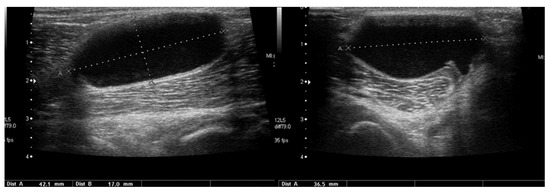

Basic Differences and Most Common Findings in Ultrasound Examinations of Musculoskeletal System in Children: A Narrative Literature Review

by Tomasz Poboży, Wojciech Konarski, Karolina Piotrowska-Lis, Julia Domańska, Kamil Poboży and Maciej Kielar

Healthcare 2022, 10(10), 2010; https://doi.org/10.3390/healthcare10102010 - 12 Oct 2022

We present basic differences in the musculoskeletal ultrasound examinations between adults and children. Examiners who deal with adults on a daily basis have shared concerns about examining children. Such concerns may arise from the different approach to child ultrasounds, but they also come [...] Read more.

We present basic differences in the musculoskeletal ultrasound examinations between adults and children. Examiners who deal with adults on a daily basis have shared concerns about examining children. Such concerns may arise from the different approach to child ultrasounds, but they also come from differences in anatomical characteristics according to developmental age. We discuss the presence of growth plates, as well as non-mineralized parts of the bones. We also refer to the pathologies most often found in ultrasounds in early developmental stages. In the PubMed database, the set of keywords: “msk ultrasound in children”, “pediatric msk sonoanatomy”, “coxitis fugax”, “pediatric Baker’s cyst”, “Baker’s cyst ultrasonography”, “bone septic necrosis in ultrasonography”, “ultrasonography in juvenile idiopathic arthritis”, and “ultrasonography in juvenile spondyloarthropathies”, was used to identify a total of 1657 results, from which 54 was selected to be included in the article. We discuss the problem of osteochondritis dissecans, Osgood-Schlatter disease, examples of ligament injuries (especially in relation to the knee and ankle joints), exfoliation of growth cartilages, osteochondroma, exudates and inflammations affecting joints, and Baker’s cysts. In this way, we have collected useful information about the most common diseases of the musculoskeletal system in children. Full article

Show Figures

Figure 1